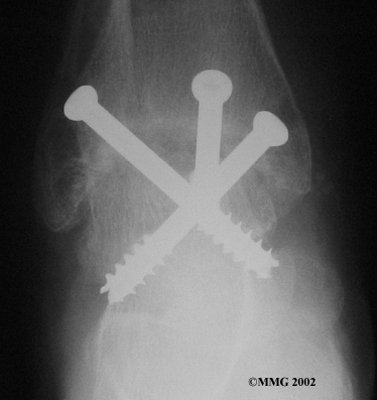

It is important when the surfaces are removed that the angles of the cut surfaces are correct. When the tibia is brought against the talus, the foot should be at a right angle to the lower leg. Once the cuts are made the bones must be held in place while they fuse. This can be done using large metal screws and metal plates if necessary. The screws are usually under the skin and are not removed unless they begin to rub and cause pain.

Inserting the screws

After ankle fusion, the physical therapists at FYZICAL Sun City North can help you learn to walk smoothly and without a limp. Although time needed for recovery varies among patients, an ankle brace will typically replace your cast after eight to 12 weeks. Your surgeon will take X-rays frequently to see if the bones are fusing together. You will probably need to use crutches during the time you wear the cast. As the fusion grows stronger, you will begin to put more weight on your foot when walking.